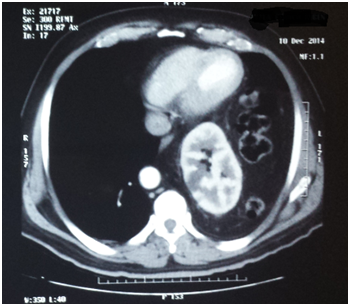

The patient attends the urology outpatient clinic because the previous week he had presented lumbar pain radiating to the right flank as well as the right iliac fossa, intermittent, without fever but with occasional constipation and flatulence. The patient attends to a private’s hospital ER and is prescribed with analgesics, however, 24hours later he presents a new pain condition and attends the same center and undergoes further complete laboratory tests that did not present any alterations. After a throaco abdominal Computerized Axial Tomography with contrast, the presence of intra thoracic ectopic kidney and left diaphragmatic hernia is observed and with a progress caused by the medical treatment administered in the hospital, the patient attends the Urology service due to the presence of left ectopic kidney. Upon arrival to the clinic, the asymptomatic patient does not show any urological pathology and turns out with normal laboratory results (Figure 1-4).

Figure 1 CT sacan show a left kidney near to the heart.